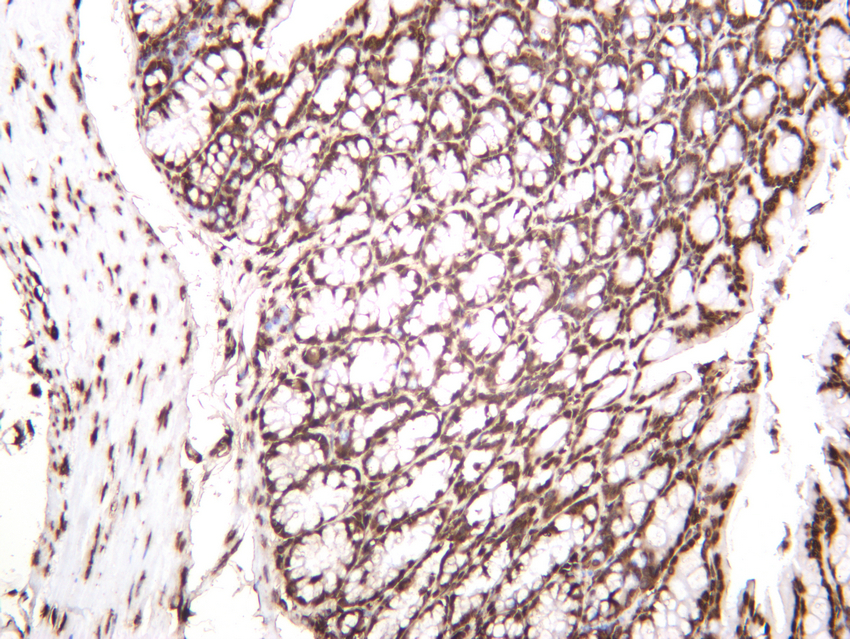

Immunohistochemical analysis of paraffin-embedded Mouse colon tissue using Histone H3 Antibody.

Immunohistochemical analysis of paraffin-embedded Rat liver tissue using Histone H3 Antibody.

Immunohistochemical analysis of paraffin-embedded Human liver tissue using Histone H3 Antibody.

Immunohistochemical analysis of paraffin-embedded Human brain tissue using Histone H3 Antibody.

Immunohistochemical analysis of paraffin-embedded Human esophagus cancer tissue using Histone H3 Antibody.